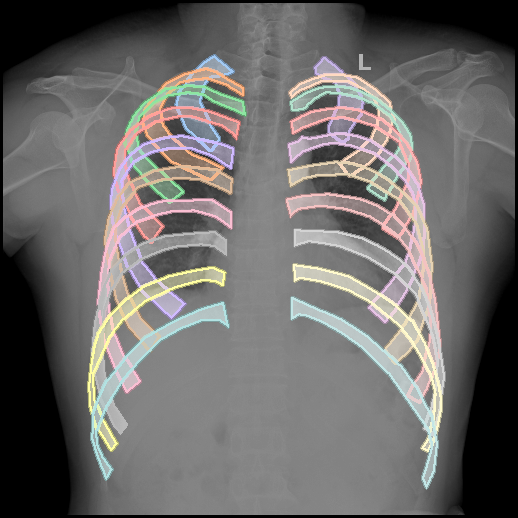

VinDr-RibCXR (public): Provides segmentation masks for all 20 ribs across 196 training and 49 validation images [nguyen2021vindr-rib]. The official validation set is used for testing.

3.2.1 Performance in Chest Region Segmentation

We evaluate segmentation performance across six tasks spanning five datasets, all focused on chest anatomy (Tab. 4). Using a linear decoder, all X-ray–specific models outperform the general-domain DINOv2 baseline. Notably, XR-0 achieves the best performance on the JSRT dataset and ranks second across all other tasks. This strong performance is particularly noteworthy given that XR-0 is trained entirely from scratch—without warm-start initialization—and uses a relatively modest dataset ( 380K images, including 220K frontal chest X-rays), in contrast to chest-specific models like RadDINO. These results highlight the effectiveness of multi-anatomy pretraining in enabling robust generalization across anatomy-specific tasks.

However, when evaluated with the UPerNet decoder (Fig. 3, CXR-0 and XR-0 under-perform relative to DINOv2 and RadDINO. We hypothesize that this discrepancy stems from differences in intermediate feature quality. DINOv2, pretrained on large-scale natural images, consistently delivers top segmentation results, while RadDINO inherits these robust features via warm-start initialization. In contrast, our models are trained from scratch, which may limit the expressiveness of intermediate representations required by complex decoders like UPerNet.

The ability of XR-0 to perform competitively with a simple linear decoder highlights its potential for deployment in resource-constrained settings. The observed architectural trade-offs further emphasize the need to align decoder complexity with the quality of learned representations for optimal performance.

| PTX | VinDr-RibCXR | VinDr-RibCXR | SIIM-ACR | JSRT | PAX-Ray++ | ||

| Models | Decoder | private | instance | semantic | PTX | ||

| DINOv2 | Linear | 30.8 | 38.7 | 73.1 | 27.8 | 82.8 | 50.0 |

| RadDINO | Linear | 38.6 | 49.9 | 73.8 | 37.0 | 86.1 | 59.3 |

| CXR-0 | Linear | 32.9 | 41.3 | 73.3 | 29.1 | 82.6 | 55.3 |

| XR-0 | Linear | 34.0 | 42.7 | 73.6 | 32.6 | 86.2 | 56.3 |

| DINOv2 | UPerNet | 62.7 | 74.5 | 87.5 | 53.5 | 95.6 | 71.8 |

| RadDINO | UPerNet | 61.4 | 73.9 | 87.4 | 53.8 | 95.6 | 71.8 |

| CXR-0 | UPerNet | 52.0 | 71.0 | 85.9 | 47.0 | 95.0 | 71.0 |

| XR-0 | UPerNet | 54.9 | 70.6 | 86.0 | 49.4 | 95.2 | 70.7 |